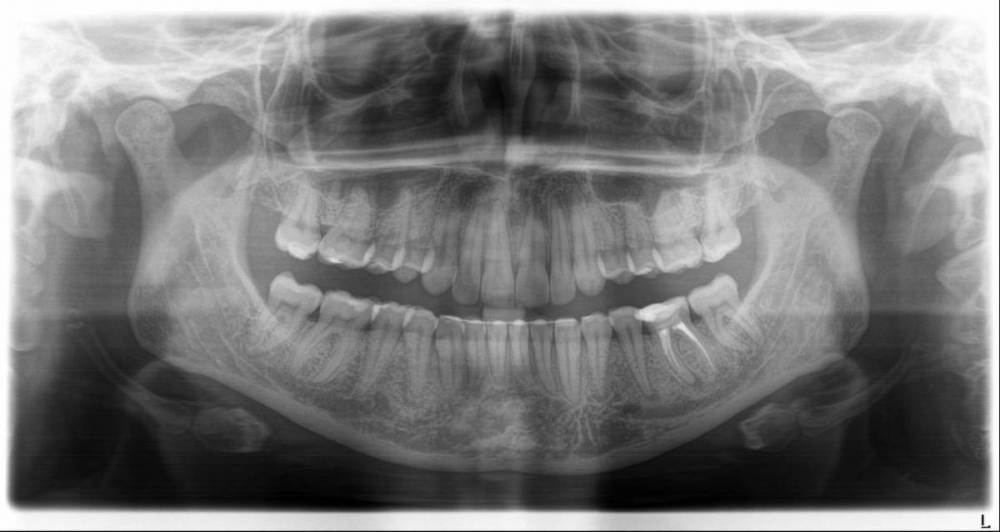

chacraborti Опубликовано 25 января, 2023 Поделиться Опубликовано 25 января, 2023 (изменено) Врач говорит что под пятеркой воспаление, квалифицирует зуб к лечению каналов. Прав ли врач? Можно ли вылечить воспаление иначе? Антибиотиками? Через кость? Через лунку при удалении рядом находящейся шестерки без нервов (она квалифицирована к удалению)? Субъективно время от времени в том районе чувствую слабую тупую боль которая может продолжаться несколько дней. потом исчезает, иногда стреляет(бывает раза 2 в день) время от времени, когда ем мороженное в том месте как будто щелкает Изменено 25 января, 2023 пользователем chacraborti Ссылка на комментарий

red_butler Опубликовано 26 января, 2023 Поделиться Опубликовано 26 января, 2023 5 часов назад, chacraborti сказал: Прав ли врач? если судить только по снимкам и Вашим жалобам то прав. Холодовую пробу проводили? 5 часов назад, chacraborti сказал: Через лунку при удалении рядом находящейся шестерки без нервов (она квалифицирована к удалению)? по снимкам вполне лечибельный зуб Ссылка на комментарий

chacraborti Опубликовано 26 января, 2023 Автор Поделиться Опубликовано 26 января, 2023 Цитата Холодовую пробу проводили? Холодовую пробу не проводили, жалоб врачу не озвучивала (прием был о судьбе шестерки). Врач квалифицировал пятерку к лечению каналов ориентируясь только на снимки: панорамный и маленький. Стоит провести холодовую пробу чтобы определить какой зуб вызывает мои жалобы? Ссылка на комментарий